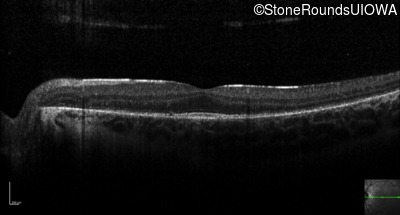

Optical Coherence Tomography - Right - 20/20 -3

Exemplar / OCT Stack

OCT Stack